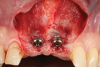

Fig 8. Surgical site after 3 months.

Figure 8

Fig 9. Flap design planning.

Fugure 9

Fig 10. Flap elevation. Note that the mid portion of the flap was de-epithelialized to be rolled between the two implants.

Figure 10

Fig 11. Split-thickness flap elevation. Note the increased soft-tissue thickness on the buccal aspects of the implants.

Figure 11

After 3 months of submerged healing, the operated area presented with limited keratinized mucosa on the buccal aspect (Figure 8). Therefore, a flap with two vertical incisions was designed starting from the palatal aspect of the two submerged implants. In addition, the mid-palatal portion of the flap was further extended toward the palatal aspect to obtain a roll flap that was de-epithelialized with a bur and eventually rolled to increase the interproximal soft tissue between the two implants (Figure 9). The flap was elevated in split-thickness fashion, with the soft tissue on top of the implants being removed to identify the cover screws (Figure 10). A substantial increase in soft-tissue thickness was observed at the buccal aspect of the implants compared to the first surgical procedure (Figure 11), when the implant fixtures were visible through a thin layer of connective tissue fibers adherent to the implant surfaces. The cover screws were removed, and temporary titanium abutments were connected.